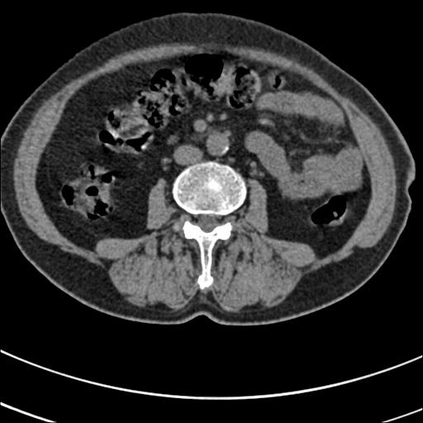

Low-Dose Computed Tomography (LDCT) technique, which reduces the radiation harm to human bodies, is now attracting increasing interest in the medical imaging field. As the image quality is degraded by low dose radiation, LDCT exams require specialized reconstruction methods or denoising algorithms. However, most of the recent effective methods overlook the inner-structure of the original projection data (sinogram) which limits their denoising ability. The inner-structure of the sinogram represents special characteristics of the data in the sinogram domain. By maintaining this structure while denoising, the noise can be obviously restrained. Therefore, we propose an LDCT denoising network namely Sinogram Inner-Structure Transformer (SIST) to reduce the noise by utilizing the inner-structure in the sinogram domain. Specifically, we study the CT imaging mechanism and statistical characteristics of sinogram to design the sinogram inner-structure loss including the global and local inner-structure for restoring high-quality CT images. Besides, we propose a sinogram transformer module to better extract sinogram features. The transformer architecture using a self-attention mechanism can exploit interrelations between projections of different view angles, which achieves an outstanding performance in sinogram denoising. Furthermore, in order to improve the performance in the image domain, we propose the image reconstruction module to complementarily denoise both in the sinogram and image domain.

翻译:降低对人体的辐射伤害的低剂量成像技术(LDCT)正在引起人们对医疗成像领域的兴趣。由于低剂量辐射导致图像质量下降,LDCT考试需要专门的重建方法或解密算法。然而,最近大多数有效方法忽略了原始投影数据的内部结构(Sintmag),这种数据限制了它们的分泌能力。罪状的内结构是罪状图领域数据的特殊特征。通过在解密的同时保持这一结构,噪音可以明显地受到限制。因此,我们建议使用Singraph Inner-Strockre变异器(SIST)来降低图像质量网络的噪音,以便利用罪状领域的内部结构来减少噪音。具体地说,我们研究染色学的CT成像机制和统计特征来设计罪状内结构损失,包括恢复高质量CT图像的全球和地方内部结构。此外,我们提议使用一种罪状变形模型模块来更好地提取罪状特征。因此,我们提议使用一种自我观察的变形结构,在罪状模型中可以利用一种杰出的域域图的性变图,从而改进了不同图像的成图。